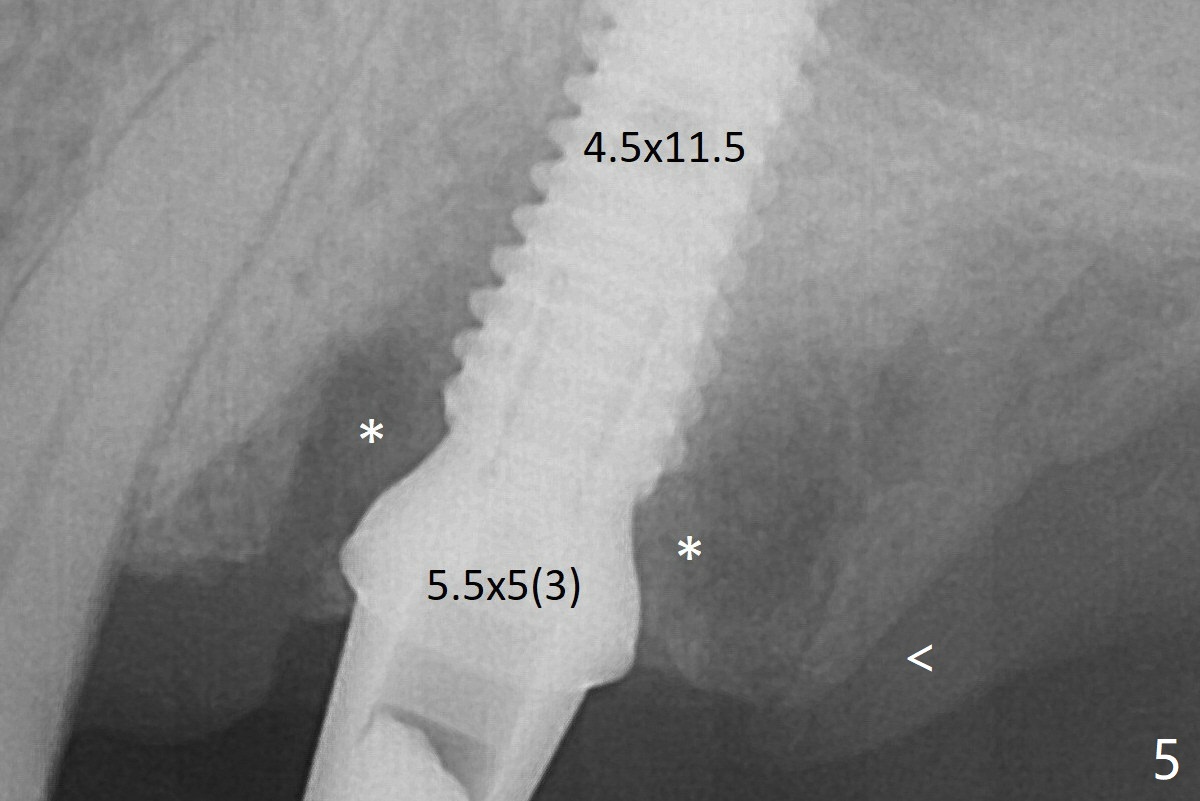

When a 4.5x11.5 mm implant is placed (>35 Ncm), palatal threads are exposed, to which autogenous bone and Vera Graft (Fig.5 *) are placed with a 5.5x5(3) mm abutment. The distal implant threads remains exposed 6 months postop; it appears that the distal socket wall (Fig.7 <) has resorbed (Fig.8). That is a probable reason that the distal threads are exposed. The sockets heal 1 year 7 months post cementation (Fig.9).